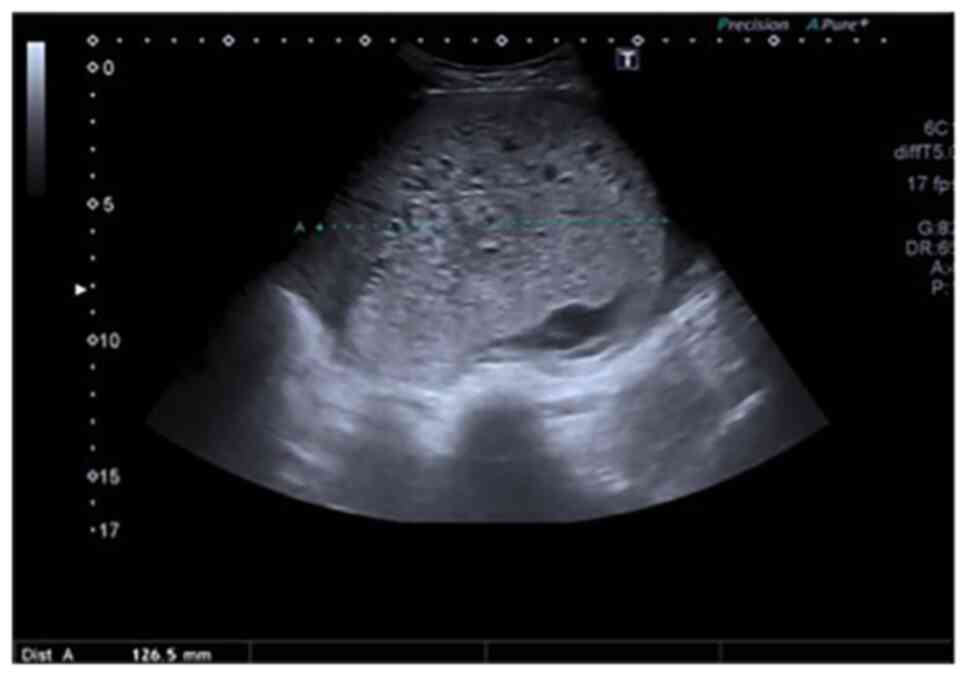

To minimise risk of developing a haemorrhage, the interventional radiology team inserted bilateral internal iliac artery balloons. A total of 2x10 ml 1% lidocaine was used as a local anaesthetic. Ultrasound guided punctures of the common femoral arteries were performed by a consultant interventional radiologist with 5-French sheaths inserted into both sides (Fig. 2). Fogarty compliant balloons were inflated in the anterior division of each of the internal iliac arteries until the flow was abolished distally. She then underwent the surgical evacuation of retained products under transabdominal ultrasound guidance. The internal os of the cervix was mechanically dilated to Hegar number 12, followed by the suction evacuation of copious amounts of products and blood, with gentle curettage under ultrasound guidance transabdominally. Following the evacuation of the uterine contents, the balloon catheters and both sheaths were removed, and arterial punctures sealed with mynx grips.

Figure 2Angiogram of the left internal iliac artery showing the branches of the uterine artery stretched around the hydatidiform mole, prior to placement of occlusion balloons. The letters LT in the image indicate the left internal iliac artery. |